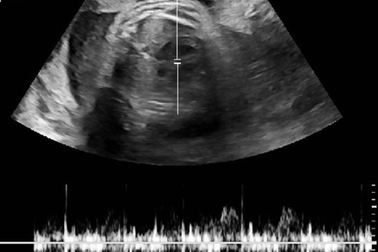

Cấy que tránh thai vẫn dính bầu, người mẹ trẻ buộc phải bỏ conSau khi cấy que tránh sau được 9 tháng, chị Liên phát hiện mình có bầu. Do đã sinh mổ 3 lần nên chị Liên buộc phải bỏ cái thai 7 tuần tuổi.